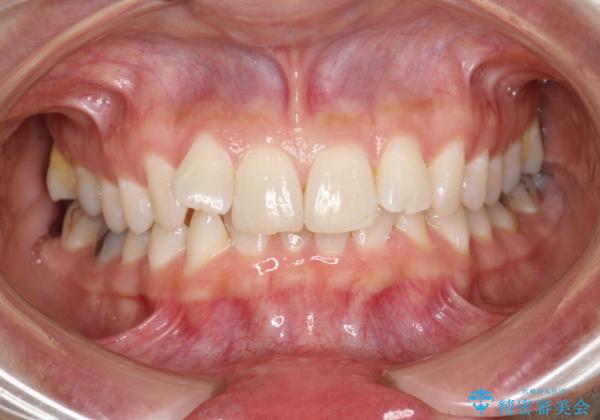

前歯のガタガタをインビザラインで矯正

- 前歯のがたつきを気にされて来院されました。

右上の前から2番目の歯が前方に大きく傾いており、下の前歯もガタガタしていました。

インビザラインにて、歯と歯のあいだをわずかに削り並べる計画としました。

しっかりとマウスピースを使用していただけたので、順調に治療を終えることができました